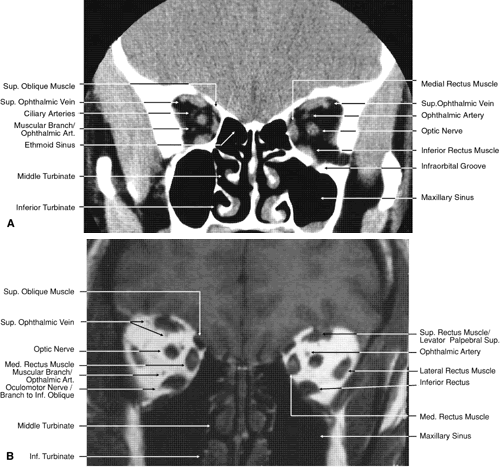

Fig. 17. Coronal images through anterior orbit. A. Computed tomography scan. B. T1-weighted magnetic resonance imaging.

Fig. 18. Coronal images through midglobe. A. Computed tomography scan. B. T1-weighted magnetic resonance imaging.

Fig. 19. Coronal images through midorbit posterior to the globe. A. Computed tomography scan.B. T1-weighted magnetic resonance imaging.

Fig. 20. Coronal images through orbital apex. A. Computed tomography scan. B. T1-weighted magnetic resonance imaging. C. Anatomic section of a cadaver head at the level of the orbital apex.